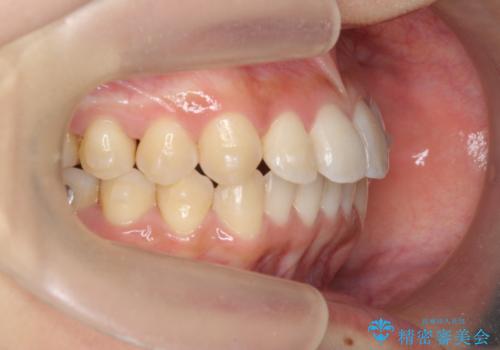

ワイヤー部分矯正治療を併用したマウスピース矯正治療

- 前歯のねじれ、深い噛み合わせ(ディープバイト)の改善を求めて来院されました。

マウスピースでは改善の難しい、歯のねじれ・ディープバイトを部分ワイヤー矯正で改善したのち、マウスピース矯正で全体の歯並びを整えていきます。

部分ワイヤー矯正を行ったことで前歯をしっかりと綺麗な歯並びへと導くことができました。